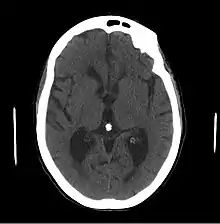

- Le scanner cérébral peut montrer une dilatation ventriculaire disproportionnée par rapport à l’atrophie corticale avec élargissement des cornes frontales et arrondissement des cornes temporales sans atrophie de l'hippocampe.

- L'IRM cérébrale, en plus de la dilatation, permet de mettre en évidence d'autres affections du système nerveux central, soit des diagnostics différentiels ou bien des facteurs affectant le pronostic du patient.